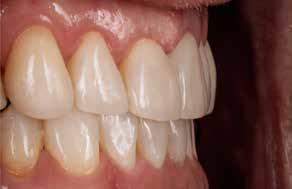

I samråd med patienten og egen tandlæge* afstemmes forventningerne, inden der bestilles refinement alignere. Nivelleringen af alle tænder i tandbuerne, smilelinje og -kurve samt den bukko-lingvale position af incisiverne foretages og efterfølges af retainers lingvalt på over- og underkæbeincisiver (Fig. 3 A-D). Hele behandlingen udføres under løbende kommunikation med patient og egen tandlæge*, der udfører den efterfølgende rekonstruktion med direkte plast (Fig. 4 A-D). Behandlingsvarigheden har været to år og to måneder, hvor ortodontien har forløbet over 21 måneder. Der har været anvendt et første sæt på 66 alignere samt yderligere to sæt med ni refinement alignere. Tandblegning og direkte plastrekonstruktion er udført af egen tandlæge* (Fig. 5 A-F).

Fig. 5. A, B. Smil og kæbeforhold før og efter. Et bredere smil med korrektion af de laterale mørke rum. C-F. Harmonisk hældning af overkæbe- og underkæbeincisiver, rekonstruktion af den tabte tandsubstans efter nivellering af gingivaniveau og optimal bukko-lingval placering til direkte plastbehandling.

5. A, B. Smile and jaw relationships before and after. A wider smile with correction of the lateral dark spaces. C-F. Harmonious inclination of the upper and lower jaw incisors, reconstruction of the lost tooth substance after leveling the gingival level, and optimal bucco-lingual positioning for direct plastic treatment.